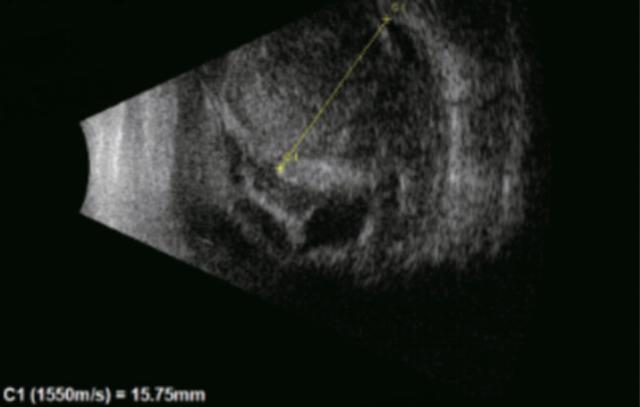

两例患者最终均实现视网膜解剖复位,两位患者术后前房恢复透明,人工晶体位置稳定,患者1的矫正视力恢复到0.15,尽管SCH的总体预后仍不乐观,但及时规范的治疗可最大限度保留,眼球结构和残存视力。

(▲患者1术后眼底图及B超)